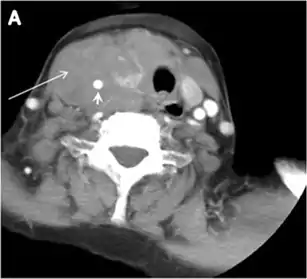

Fig. 11. Thyroid non-Hodgkin's large B-cell lymphoma in a 66-year-old female patient. an Axial enhanced neck CT scan demonstrates left thyroid lobe and isthmus homogeneously hypodense and minimally enhancing mass (white arrows). This lesion invades the prevertebral muscles (black arrows). Note the multiple enlarged level V lymph nodes (white arrowheads). b Post-treatment image shows significant reduction in size and mass effect of the left thyroid infiltrative mass, with almost complete resolution of the left cervical lymphadenopathy.[1]

Thyroid lymphoma represents about 5% of thyroid malignancies. Non-Hodgkin's lymphoma is the most common type and can be secondary to generalized lymphoma or a primary tumour. Primary thyroid lymphoma usually pre-exists with Hashimoto's thyroiditis. On CT scans with and without contrast, lymphomas tend to have low attenuation values. Thyroid lymphomas have a variable appearance and mostly manifest as a solitary mass (80%). They may also manifest as multiple nodules (15% to 20%) or as a bulky mass replacing the entire gland with extra-thyroid extension (Figs. 11 and and12).12). The presence of cervical lymphadenopathy supports such a diagnosis. Although it is uncommon, tumour necrosis has been reported.[1]